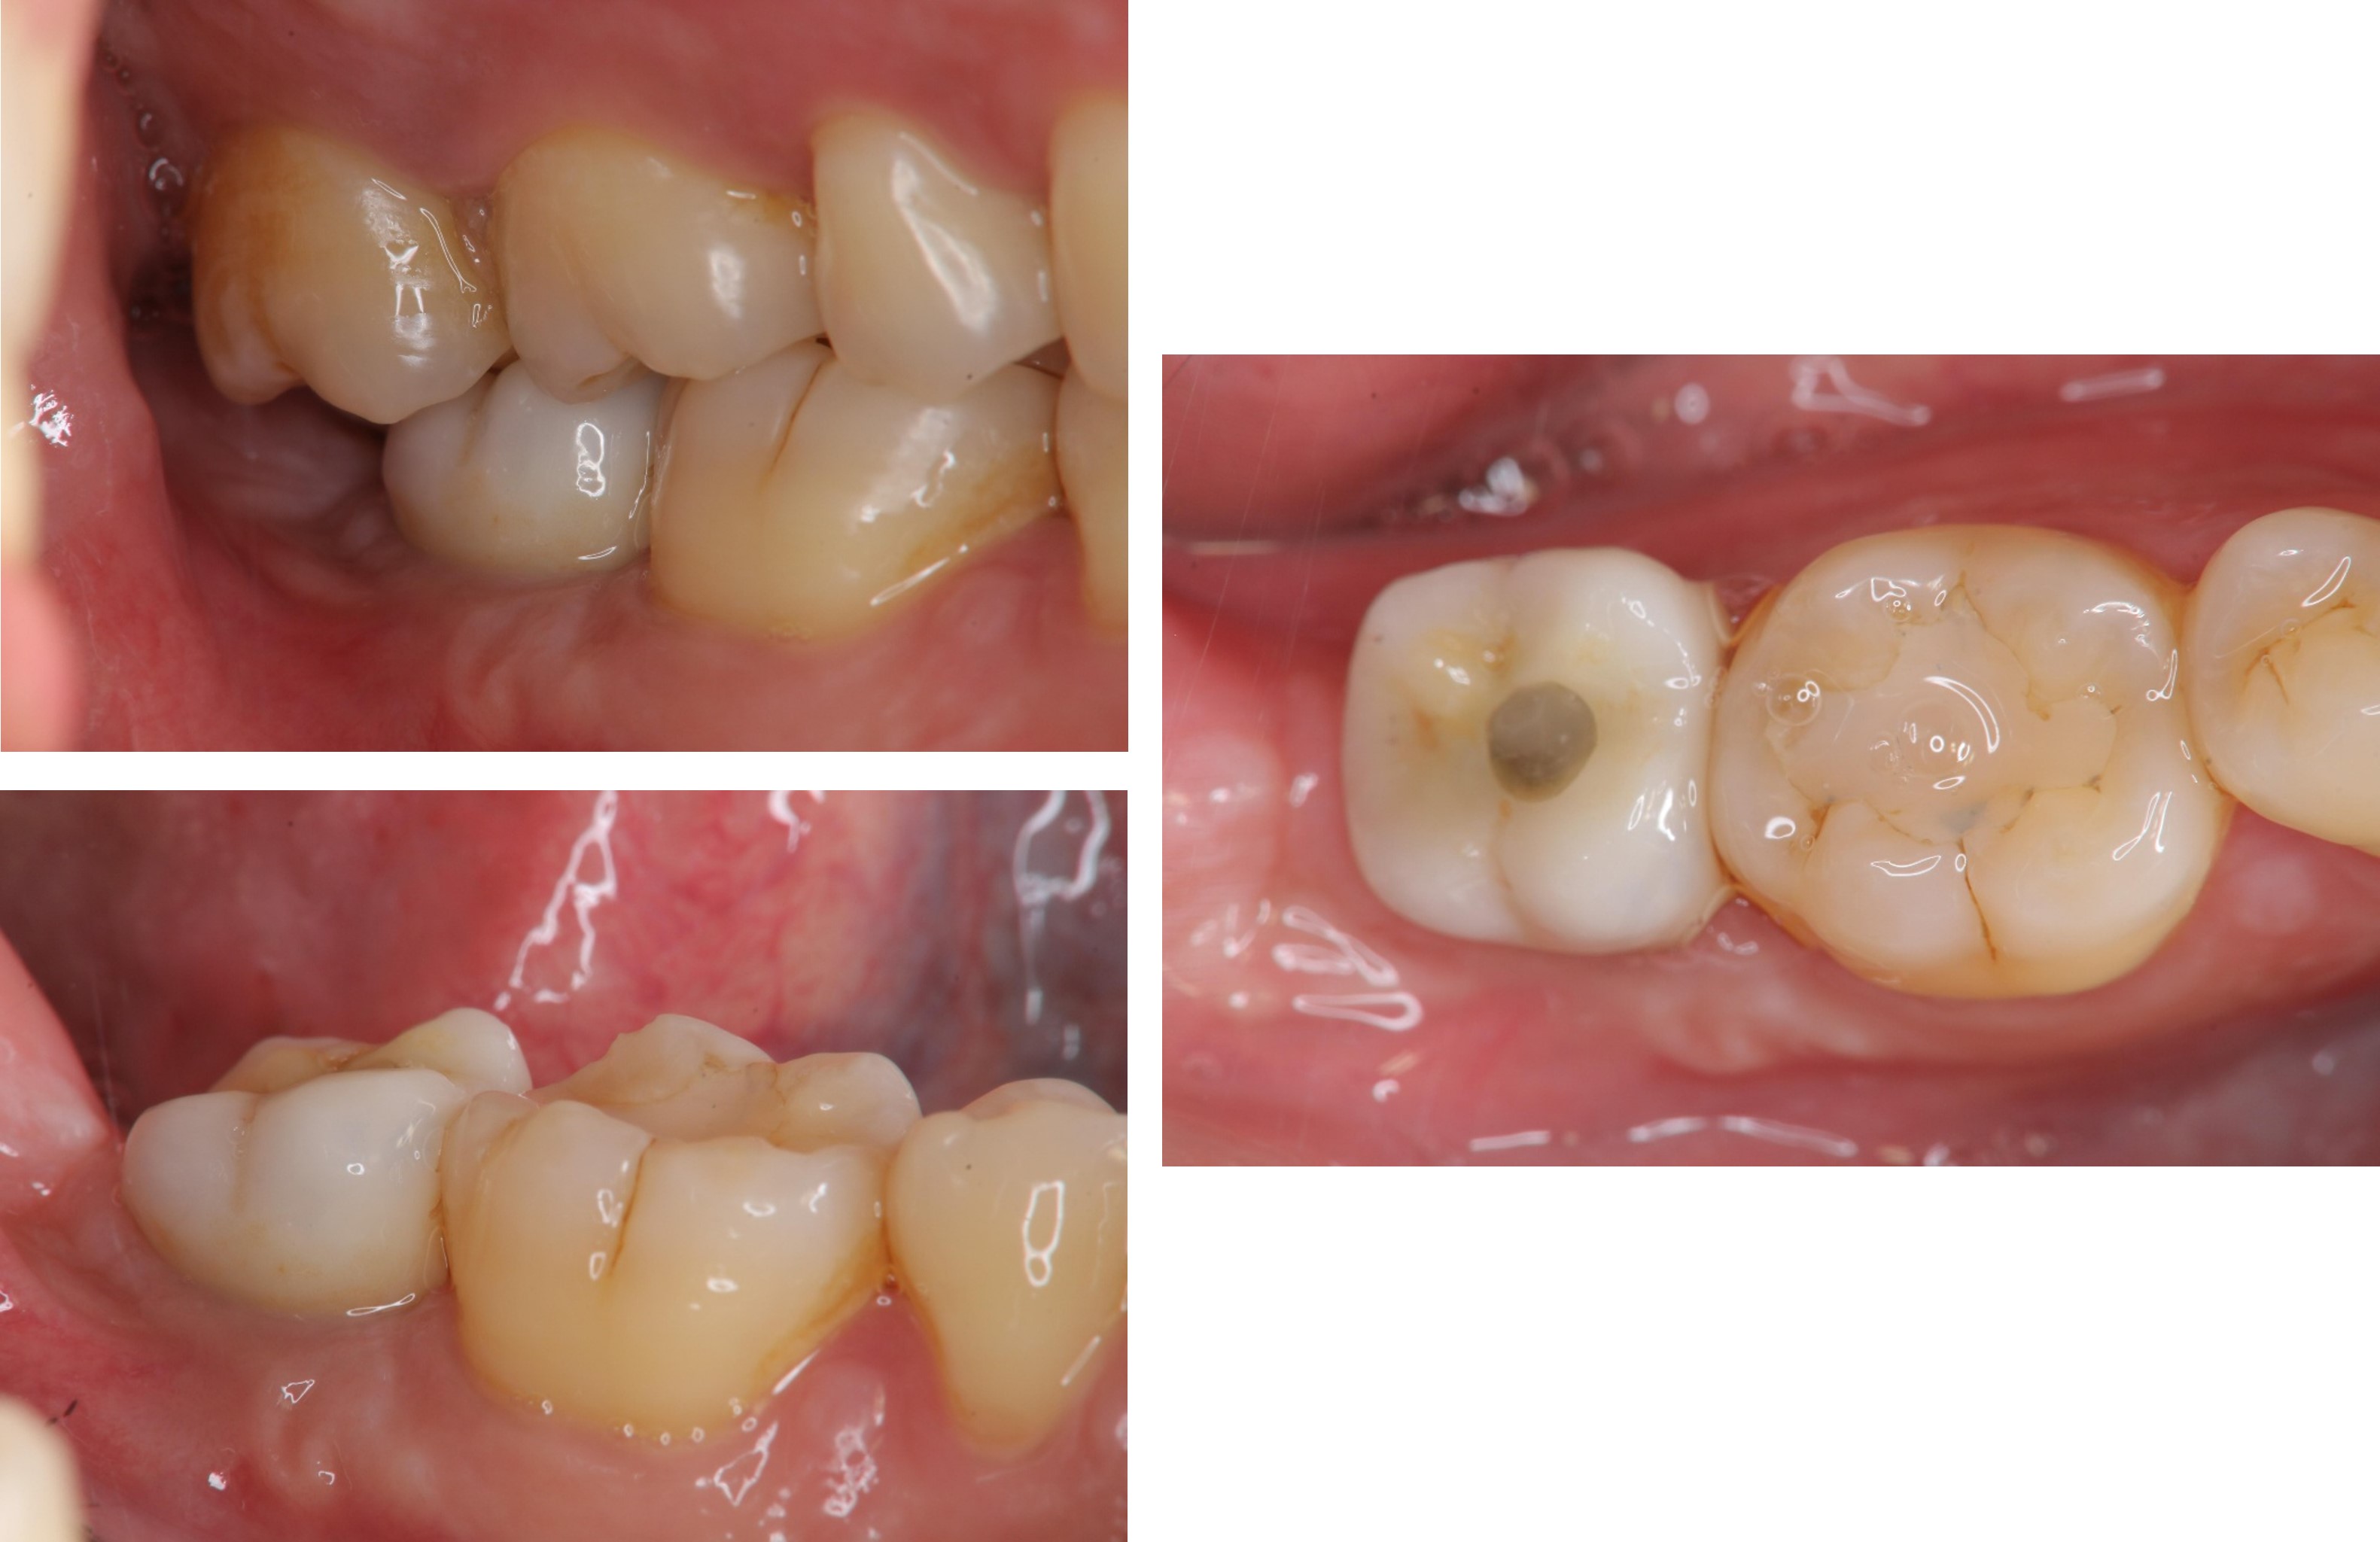

治療後,咬合牙周適應良好

治療後,密合度良好